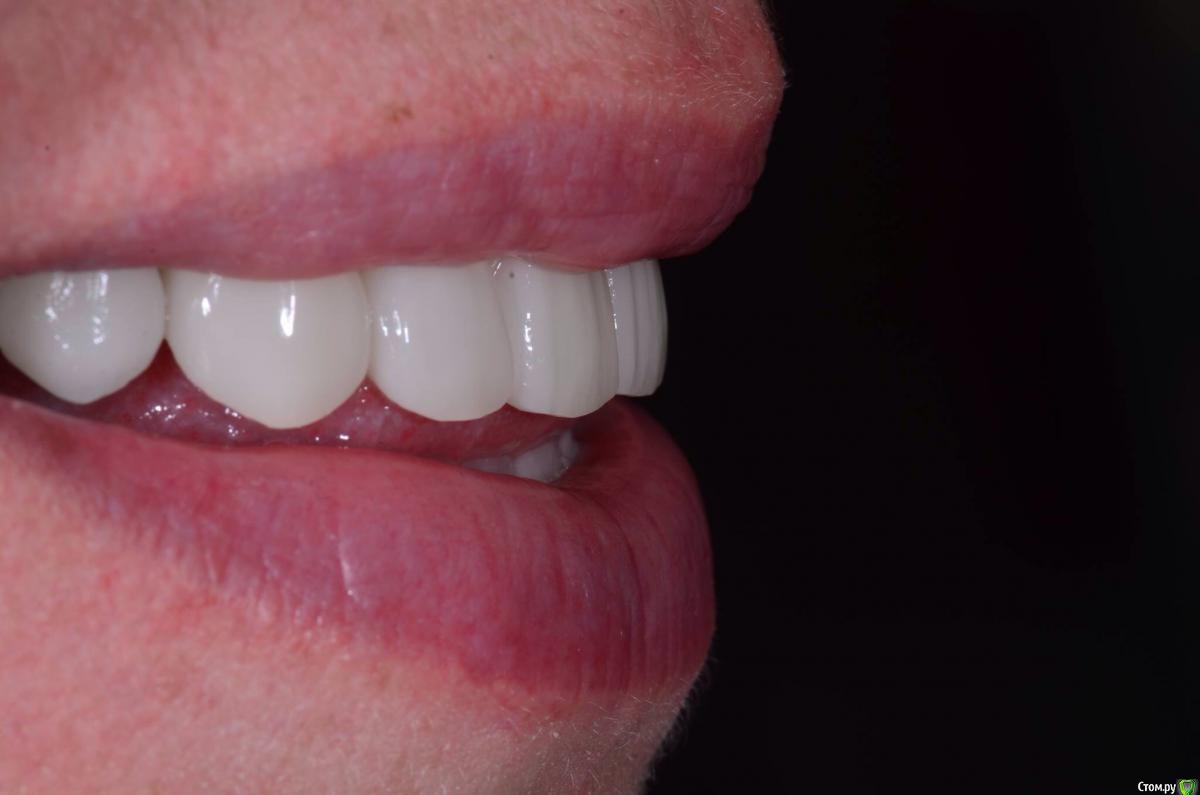

togrul Опубликовано 4 апреля, 2016 Поделиться Опубликовано 4 апреля, 2016 Добрый вечер коллеги. Восстановили зубы безметалловыми коронками Емах зубы и Циркон наслоением на имплантатах. 9 Ссылка на комментарий

togrul Опубликовано 5 апреля, 2016 Автор Поделиться Опубликовано 5 апреля, 2016 Все фотографии в день фиксации. 3 Ссылка на комментарий

alekszander Опубликовано 5 апреля, 2016 Поделиться Опубликовано 5 апреля, 2016 Техническая часть хорошая - ваша не очень.Не в обиду:1. Зачем коронки керамику на металлические супраструктуры? Не проще на стандартный абатмент напрессовать керамику? Или куда лучше циркон даже цельный.2. зуб 2.4(вроде) внедрение в биоширину,там есть показания для удлинения.(про разность зенитов,как в случае 1.1,2.1 - как и в большинстве это фетиш врачей) 3. На НЧ нужна мягкотканная+пародонтолог. лечение, с таким пародонтом кариес в рецидиве будет год два(надеюсь ошибаюсь)4. слишком рваные края препа(свой выложу в одной из тем), фотки хорошие, а работаете в оптике?5. Совет(опять же не в обиду) - не теряйте время на фто, когда стоят нити! Там счет на минуты.Я не в плане придраться, а просто акцентировал внимание на то, что мы не видим, когда работаем сами. Ссылка на комментарий

togrul Опубликовано 5 апреля, 2016 Автор Поделиться Опубликовано 5 апреля, 2016 1 Что плохого в титановых абатментами? Почему я должен использовать стандартные абатменты? В полную анатомию циркон не делаю . Вы уверены в 100% правильности восстановления окклюзии? Я нет . 2 . С биошириной все хорошо удлинять ничего не нужно на следующей неделе покажу. 3 Пациент отказался от пластики никакого кариеса там не будет. С чего там развиваться кариесу? Вы не проводите такое восстановление если пациент отказывается от пластики?4 я только на нижнем премоляре вижу рваный край уступа. Работаю в оптике.5 фото делается 2 минуты и никаких проблем в этом не вижу . Так как не использую гемостатик Спасибо . Ссылка на комментарий